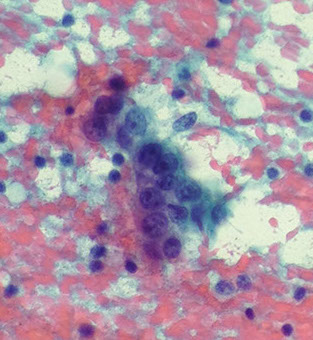

Mammary Analogue Secretory Carcinoma (MASC)

Rare, recently described neoplasm that resembles secretory carcinoma of the breast and occurs in the parotid glands of older men

- previously recognized as acinic cell carcinoma or adenoca, NOS

Cyto: Dispersed / loosely cohesive cells in papillary or pseudopapillary arrangement c large polygonal cells c lots of vacuolated reddish cytoplasm and indistinct cell borders and bland round nuclei

- extracellular mucoid material common

Genes: ETV6-NTRK3 rearrangement

Px: similar to low-grade salivary gland tumors